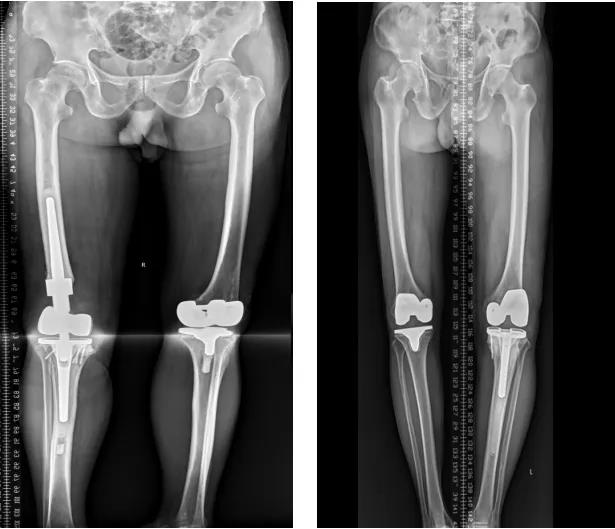

(四)膝关节置换术后关节翻修术

膝关节外科技术力量雄厚,科室配备医护人员30人,其中,主任医师5名,副主任医师3名,主治医师3名,住院医师4名,博士1名,硕士研究生4名。开放床位48张。该科擅长对膝关节严重创伤(包括股骨远端骨折、髌骨骨折、胫骨平台骨折等)、膝骨关节炎阶梯化治疗、保膝治疗、膝关节微创单髁置换术、全膝关节置换术、膝关节翻修术具有丰富的临床诊疗经验,追求微创、无痛、快速康复。对膝关节骨性关节炎采取阶梯化治疗方案,坚持中西并重、内外兼治的原则,取得满意的治疗效果。早期利用中医中药的传统优势,使用中医外治法,例如烫熨治疗、中药涂擦、雷火灸、中药塌渍等,同时辩证内服本院中药制剂及内服方药以及配合西药治疗,开展健康教育,运用运动疗法、物理治疗等辅助支持;中期开展软骨修复、截骨术、单髁置换术、髌股关节置换术等;对于终末期的膝关节OA采用全膝关节置换术。【膝关节外科主要特长】 (一)膝骨关节炎高位截骨术